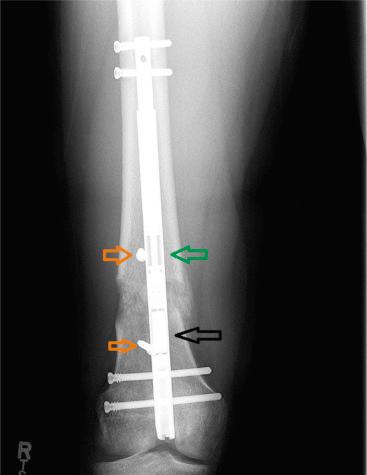

In contrast to external fixation, the ILN can only be used for axial lengthening or compression but cannot be used for gradual deformity correction. If the angular and/or translational deformity can be safely corrected acutely, then the ILN may be used. Acute correction of angulation and translation in the coronal and sagittal planes and rotation in the axial plane may be accomplished with the assistance of adjunct techniques, including fixator-assisted nailing (FAN) and blocking screws ( Fig. 27.1 ). Once the deformity has been corrected and the ILN is in place, DO may follow, but a longer latency and slower distraction is advisable because of the increased degree of periosteal disruption during acute deformity correction.

Fig. 27.1, Acute correction of valgus deformity from posttraumatic growth arrest was performed, and then gradual lengthening followed. Blocking screws (orange arrows) were placed in the concavity of the deformity. The magnet (black arrow) and distraction rod with 20-mm lengthening (green arrow) are seen.